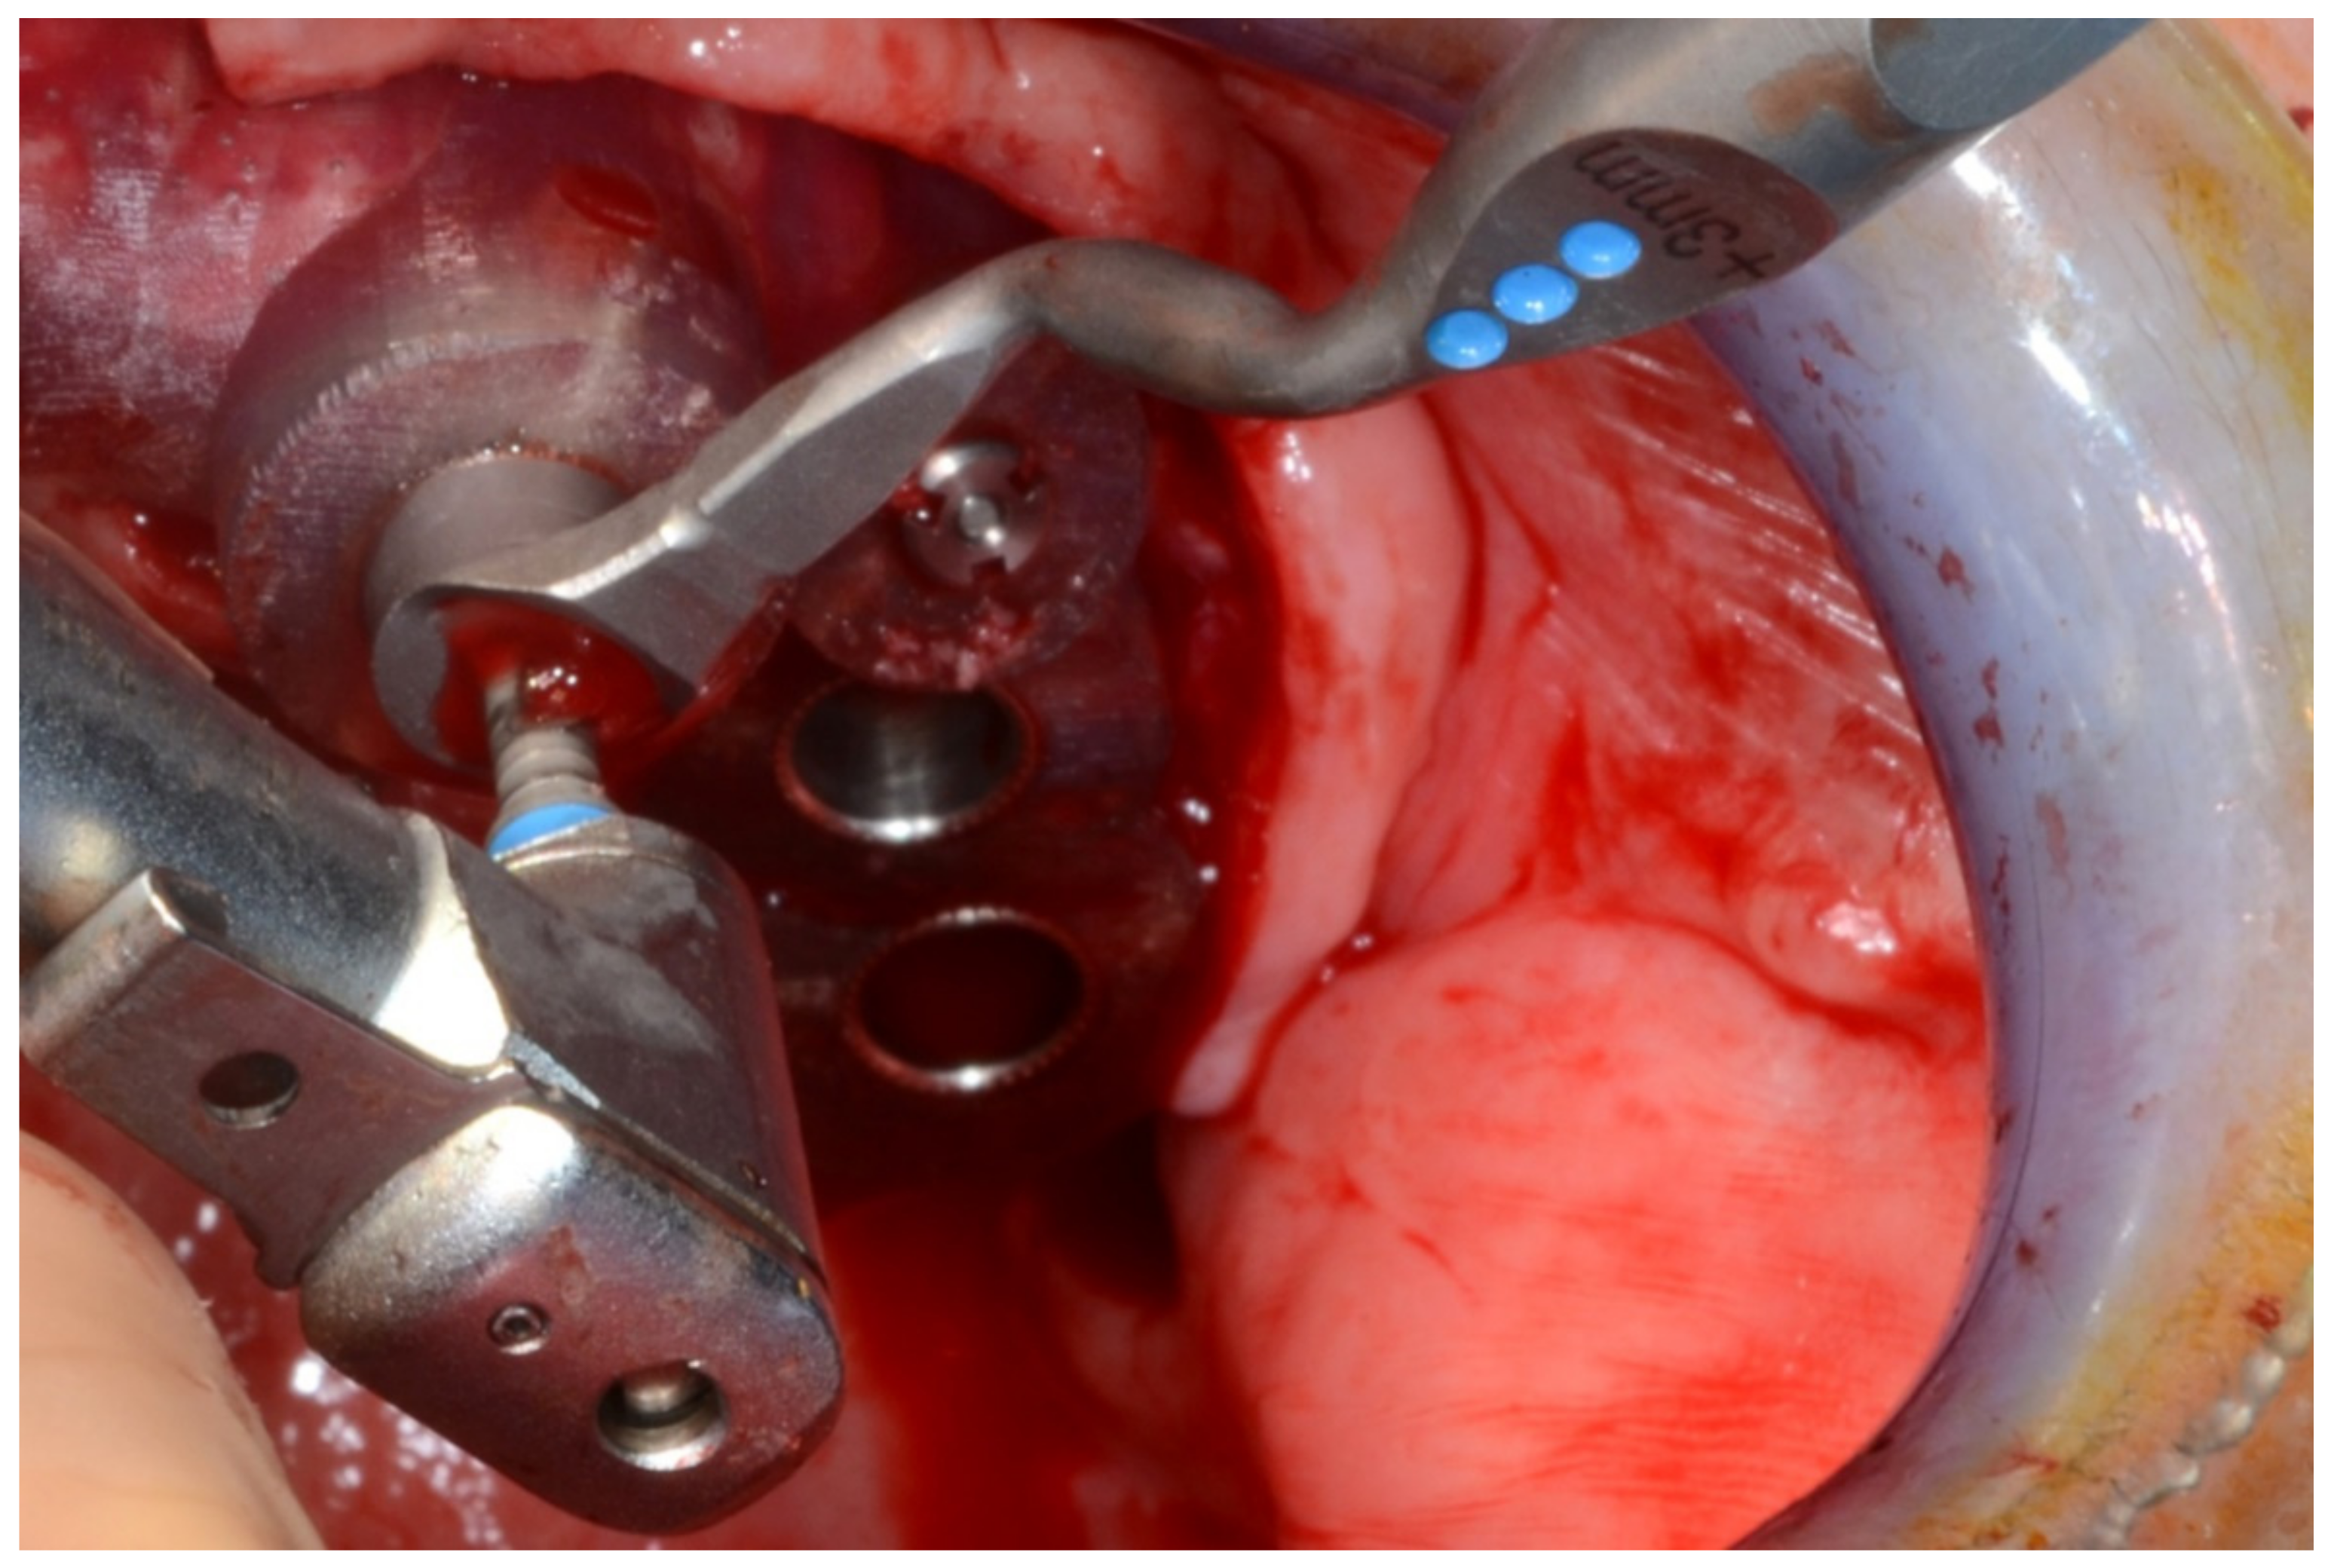

6.3.4. Intra-Operative Documentation:

In August 2019, four guided dental implants were placed at sites # 34, # 31, # 41, and # 44 (Figure 35 and Figure 36).

Figure 35.

Implant bed preparation by using guided drills inserted into specific ad hoc drill handles.

Figure 36.

Mandibular implants in place.